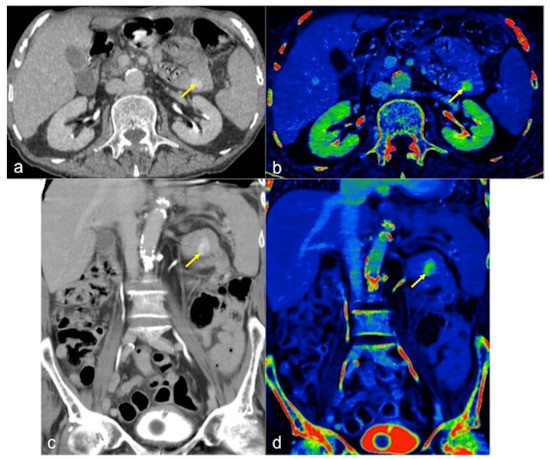

2.4. Dual-Energy CTA (DECTA)

- Trabzonlu, T.A.; Mozaffary, A.; Kim, D.; Yaghmai, V. Dual-energy CT evaluation of gastrointestinal bleeding. Abdom. Radiol. 2020, 45, 1–14. [Google Scholar] [CrossRef] [PubMed]

- Parakh, A.; Macri, F.; Sahani, D. Dual-Energy Computed Tomography: Dose Reduction, Series Reduction, and Contrast Load Reduction in Dual-Energy Computed Tomography. Radiol. Clin. N. Am. 2018, 56, 601–624. [Google Scholar] [CrossRef]